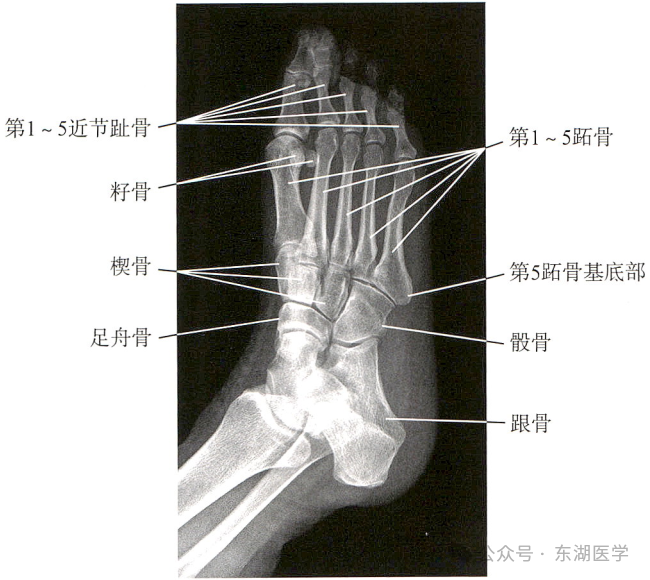

足以骨骼为支架,包括7块跗骨、5块跖骨、14块趾骨,彼此间借关节和韧带相连接。

成人足正、斜位X线解剖

1. 甲粗隆;2.踇趾远节趾骨;3. 趾间关节;4.踇趾近节趾骨;5. 第1跖骨头;6. 籽骨;7. 第1跖骨干; 8. 第1跖骨基底部;9. 内侧楔骨;10. 中间楔骨;11. 外侧楔骨;12.足舟骨;13. 距骨;14.远节趾骨;15.中间趾骨;16. 近节趾骨;17. 跖趾关节;18.第2跖骨基底部;19.第3跖骨基底部;20.第4跖骨基底部;21.第5跖骨基底部;22.骰骨;23. 跟骨